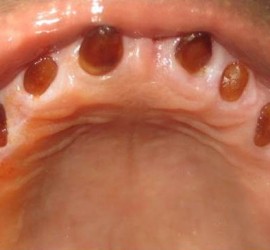

Лечение пульпита. При лечении пульпита перед врачом встают следующие задачи: избавление больного от болевых ощущений, ликвидация инфекционно-токсического очага в пульпе зуба, восстановление формы и функции зуба. Первую помощь больному острым пульпитом может оказать средний медработник или врач любого другого профиля. Она заключается в назначении внутрь обезболивающих препаратов типа анальгина, амидопирина, […]